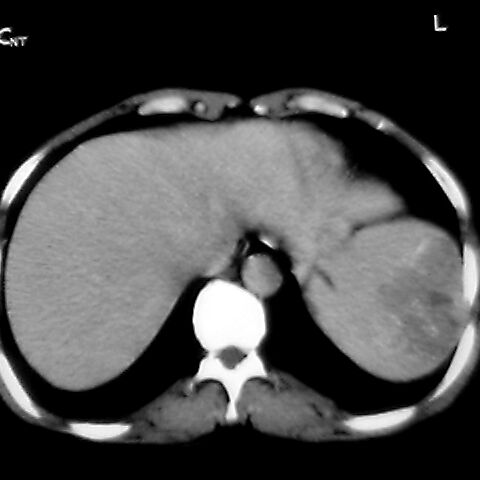

女 48岁 食道癌术前体检发现脾占位。

脾胀内部巨大低密度肿块,边界清或不清,中心坏死,轻度增强,内见散在钙化,结合食道癌病史多考虑:转移癌.

1肝右下叶小囊肿2右肾上极囊肿或错构瘤3脾脏不典型血管瘤可能性大.

脾脏低密度灶伴钙化,增强化明显,中心见液化坏死灶,强化延时明显。考虑血管瘤。转移瘤待排。